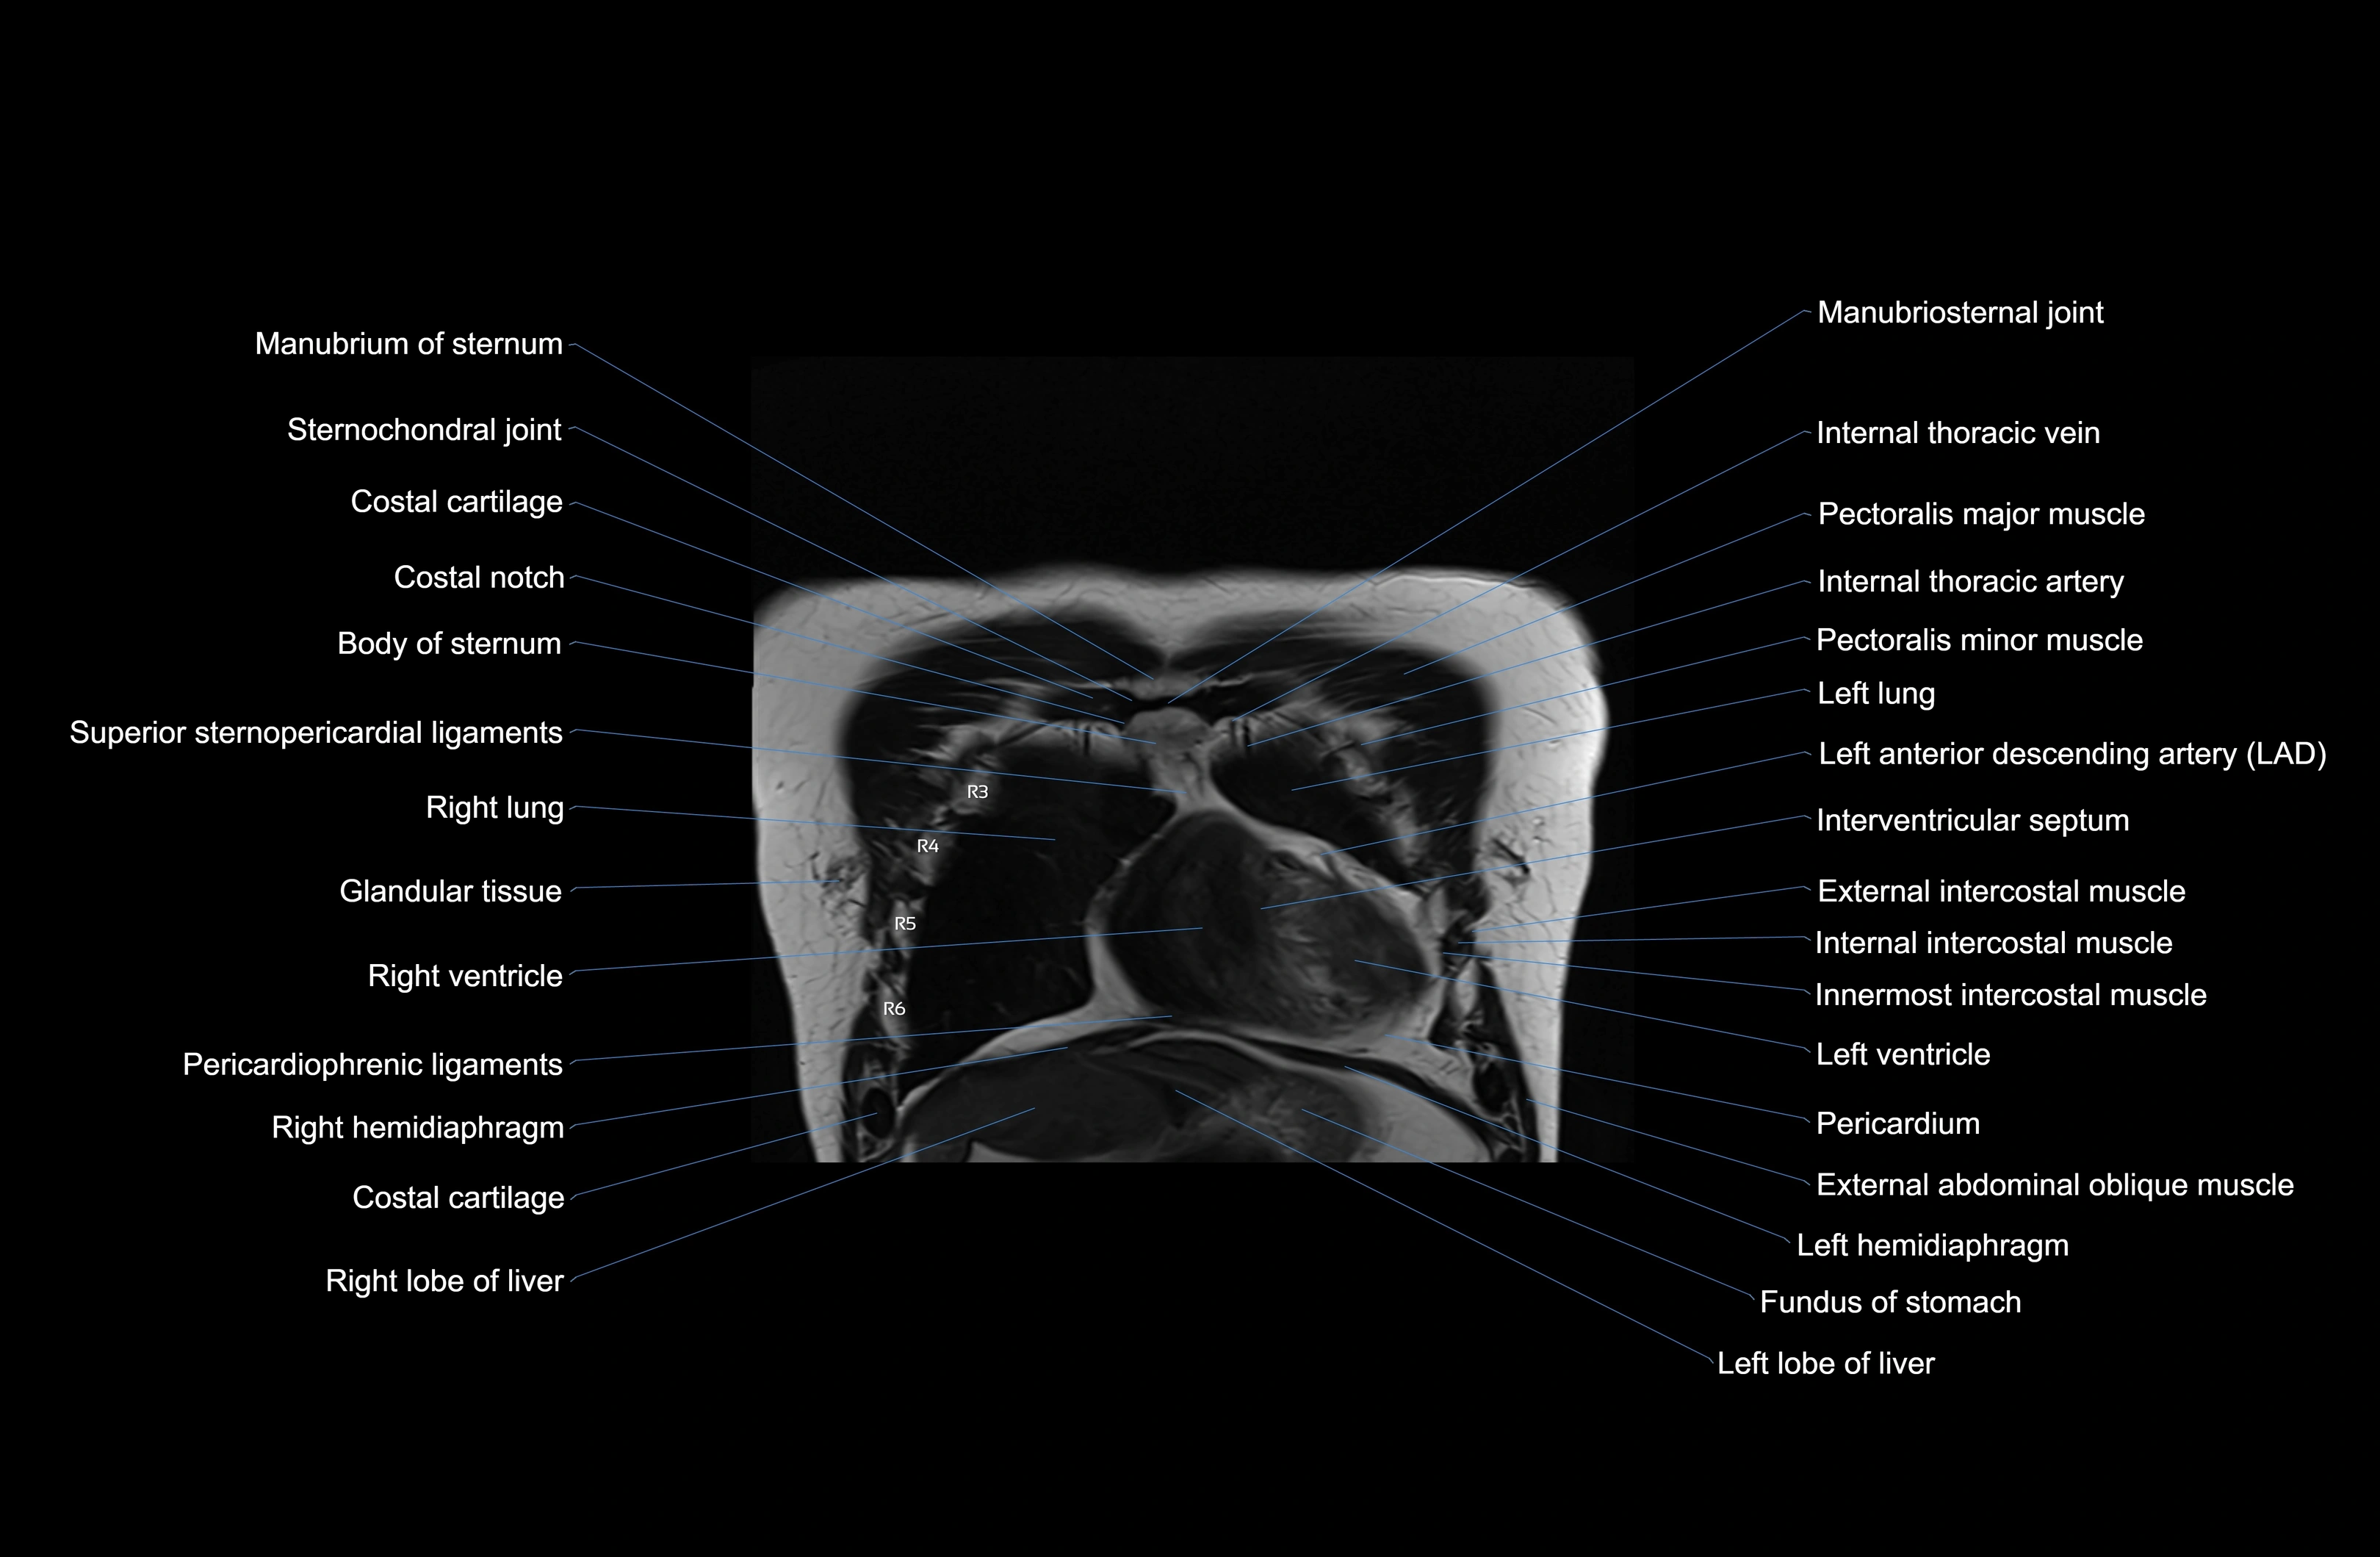

- T (Thoracic spine)